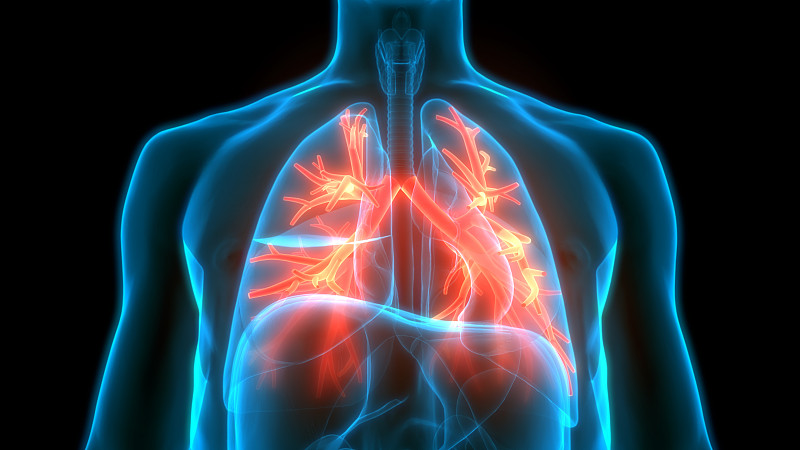

人体呼吸系统肺解剖学详情

JPG